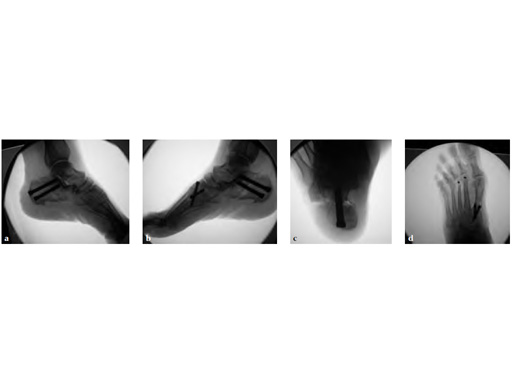

A medial displacement osteotomy of the calcaneus and transfer of the tendon of the flexor digitorum longus to the navicular fixed with an interference screw were performed (see Fig 2a-c). A fusion of the first medial cuneiformmetatarsal I, II, and III modified. Weil osteotomy was performed as well.

The talar axis is aligned to the midshaft of the first metatarsal (see Fig 3a-d).